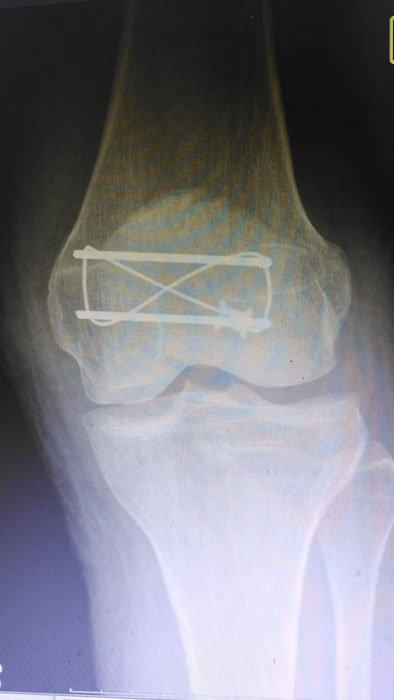

隨州新聞網訊 (通訊員王靜、陳勇)為深入推進緊密型醫共體建設,切實讓轄區群眾在家門口就能享受到優質、便捷的醫療服務,以醫療便民舉措為優化營商環境注入健康活力,3月31日中午,何店鎮中心衛生院(隨州市曾都區人民醫院何店分院)依托醫共體資源優勢,特邀曾都區人民醫院脊柱創傷外科主任徐三軍到該院,成功為一名47歲髕骨骨折患者實施髕骨骨折切開復位內固定手術,用專業診療守護群眾健康,用務實行動踐行便民宗旨。

精湛施術 安全有序,守護患者健康

手術現場,徐三軍主任憑借多年積累的臨床經驗和嫻熟的手術技巧,精準完成骨折復位、鋼板內固定、傷口縫合等一系列關鍵操作,動作規范流暢、精準高效,最大限度減少手術創傷。該院外科醫護團隊全程密切配合、協同發力,嚴格按照手術規范操作,全程嚴密監測患者心率、血壓等生命體征,及時應對術中各類突發情況,全力保障手術安全。此次手術全程順利,術中出血量少,患者生命體征始終平穩,術后患者順利安返病房,為后續康復治療奠定了堅實基礎。